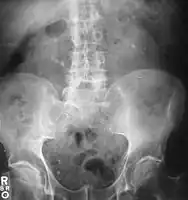

Otherwise a noncontrast helical CT scan with 5 millimeters (0.2 in) sections is the diagnostic method to use to detect kidney stones and confirm the diagnosis of kidney stone disease.[13][47][51][52][7] Near all stones are detectable on CT scans with the exception of those composed of certain drug residues in the urine,[53] such as from indinavir. Calcium-containing stones are relatively radiodense, and they can often be detected by a traditional radiograph of the abdomen that includes the kidneys, ureters, and bladder (KUB film).[53] Some 60% of all renal stones are radiopaque.[51][54] In general, calcium phosphate stones have the greatest density, followed by calcium oxalate and magnesium ammonium phosphate stones. Cystine calculi are only faintly radiodense, while uric acid stones are usually entirely radiolucent.[55]

Bilateral kidney stones can be seen on this KUB radiograph. There are phleboliths in the pelvis, which can be misinterpreted as bladder stones. -